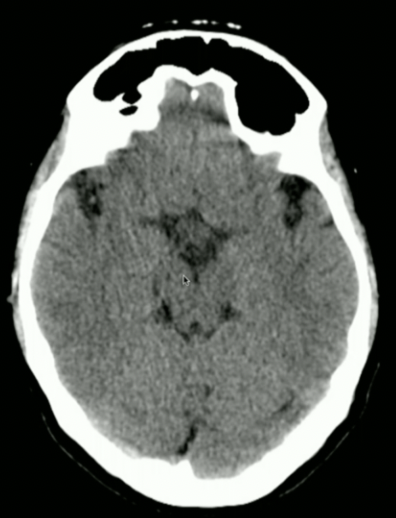

<p>What is the mouse Pointing to? + What does it create?</p>

What is the mouse Pointing to? + What does it create?

• Anterior Horn of Lat. Ventricle

• Houses Choroid Plexus → Creates CSF

• IF: Caudate nucleus swells → Impacts Lat. Ventricle → Huntingtons Disease